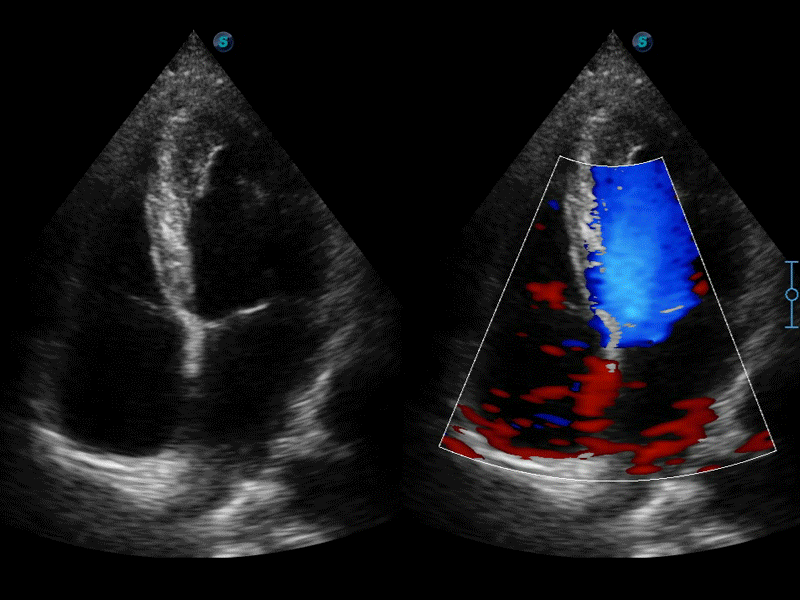

高分辨率血流成像技术提高了对低速血流信号的检测能力。在提高空间分辨率的同时,也克服了血流外溢现象,为用户提供更加真实的血流动力学信息。